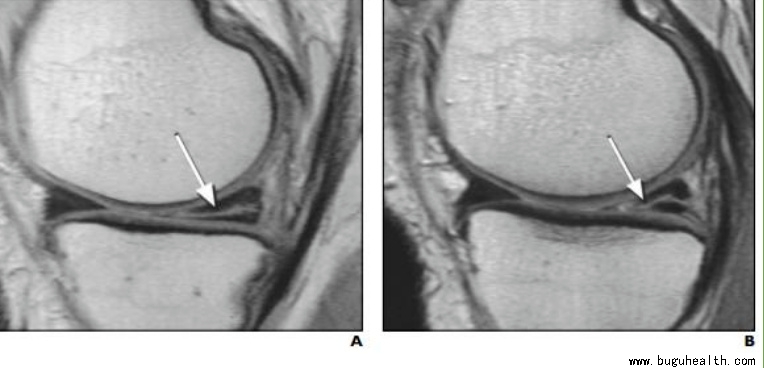

根据磁共振上,半月板的异常表现不同,我们将半月板损伤分为1-3级。其中:

1级损伤:是指半月板最轻微的病变,只是“垫子”里面出了一点点小问题,垫子外观看还是完全正常的,表面都很光滑没受损。

2级损伤:是指半月板中度的病变,损伤范围比1级要大,但是损伤都在内部,没有累及到半月板表面,没有通关节,半月板的表面依旧是光滑完整的。

3级损伤:是半月板较为严重的损伤,指半月板的撕裂样损伤,已经累及到表面,半月板表面不光滑了撕开了。

1级和2级的半月板损伤,都是首选保守治疗(休息、理疗、服药、关节内注射),不用手术;而3级半月板损伤,尤其是年轻人的急性损伤,一般都需要手术,而且需要尽快手术。